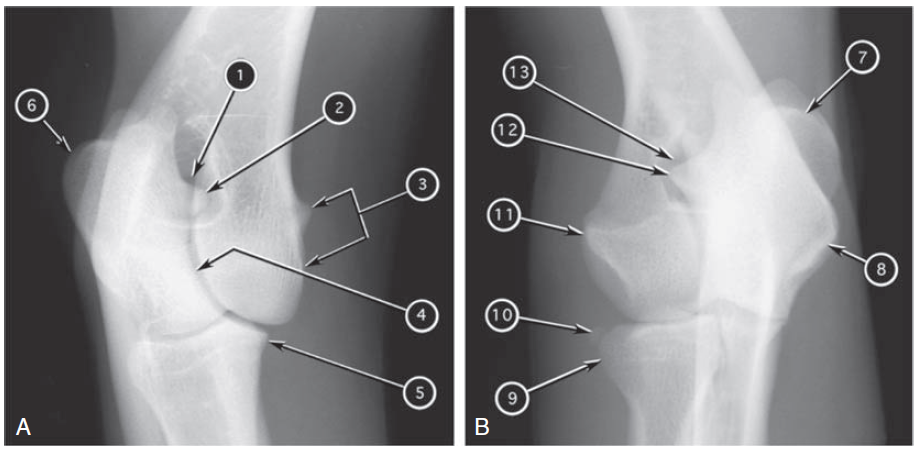

Q

Craniolateral-caudomedial oblique (A) and craniomedial-caudolateral oblique (B) radiographs of canine elbow joint

What number?

- Supratrochlear foramen of humerus (one on each radiograph)

- Anconeal process of ulna (one on each radiograph)

- Tuber olecrani (one on each radiograph)

- Medial epicondyle of humerus (one on each radiograph)

- Lateral epicondyle of humerus

- Trochlear notch of ulna

- Medial coronoid process of ulna

- Head of radius

- Sesamoid bone of supinator muscle (inconstant)

A

1. and 13. Supratrochlear foramen of humerus

2. and 12. Anconeal process of ulna

3. and 8. Medial epicondyle of humerus

4. Trochlear notch of ulna

5. Medial coronoid process of ulna

6. and 7. Tuber olecrani

7. Head of radius

8. Sesamoid bone of supinator muscle (inconstant)

9. Lateral epicondyle of humerus